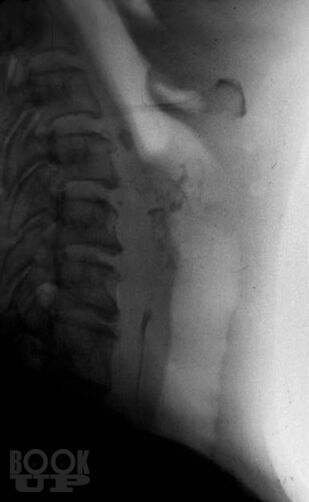

Книга П.В. Власова посвящена традиционным методам рентгенологического исследования пищеварительного тракта. В последние 20 лет периодическая печать заполнена публикациями, посвященными новым, модным и актуальным вопросам применения новейших методов лучевой диагностики, таких как ультрасонография, компьютерная и магнитнорезонансная томография. Между тем как подавляющее большинство рентгенологов в своей практической работе используют традиционные методы рентгенологического исследования, являющиеся базовыми, первичными в клинической диагностике различных заболеваний.

Дефицит литературы по вопросу ранней и своевременной диагностики заболеваний пищеварительного тракта является основной причиной недостаточной квалификации преподавателей и практических врачей, а следовательно, причиной недообследования больных, ошибочной и запущенной диагностики.

Книга восполняет существенный пробел в учебной литературе. Богатый опыт научной, практической и педагогической работы позволил авторскому коллективу, возглавляемому известным рентгенологом, профессором П.В. Власовым осветить широкий круг вопросов, касающихся традиционных методов лучевой диагностики.